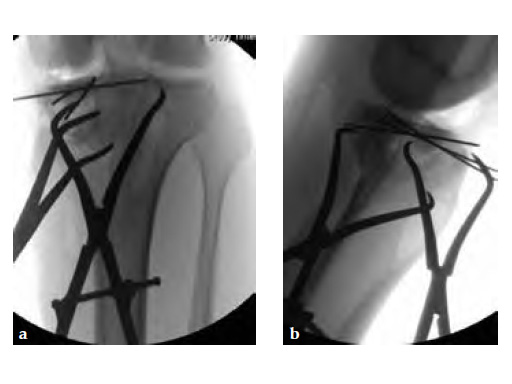

A 33-year-old male was involved in an altercation and suffered a gun shoot wound to his knee

Case provided by Brent Norris, Tulsa, USA.

Initially taken for incision and drainage and then ORIF . Patient placed in a floppy lateral position with the effected lower extremity externally rotated (opposite hip and shoulder bumped up about 3040) allowing exposure of the posterior medial knee. A posterior medial and an anteromedial incision were used to repair the fracture with a 67 cm skin bridge.